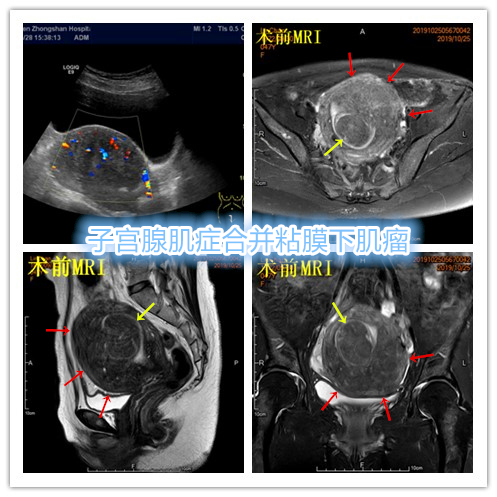

例3

中年患者,发现“子宫腺肌症”10年余,近5年痛经、月经量增多等症状明显加重,导致贫血,严重影响生活质量。MRI检查显示子宫明显增大,子宫前壁明显增厚,合并粘膜下子宫肌瘤。术前诊断为子宫腺肌症合并粘膜下子宫肌瘤。

- 经桡动脉入路UAE,术后患者无需长时间卧床、下肢制动,可明显提升术后舒适度,减少术后并发症,促进术后快速康复!